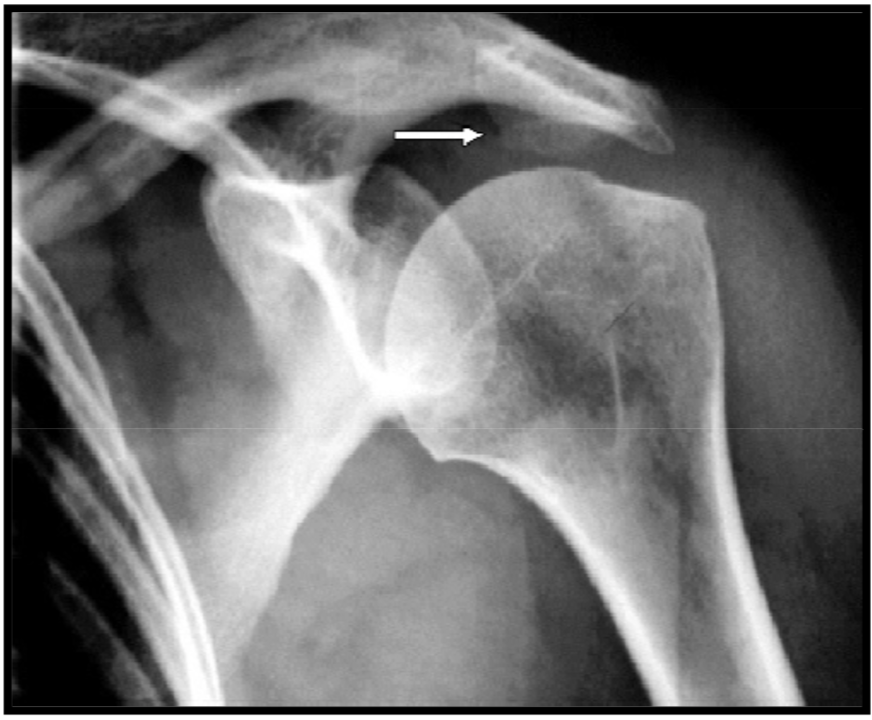

Acromial hook

variation anat normal